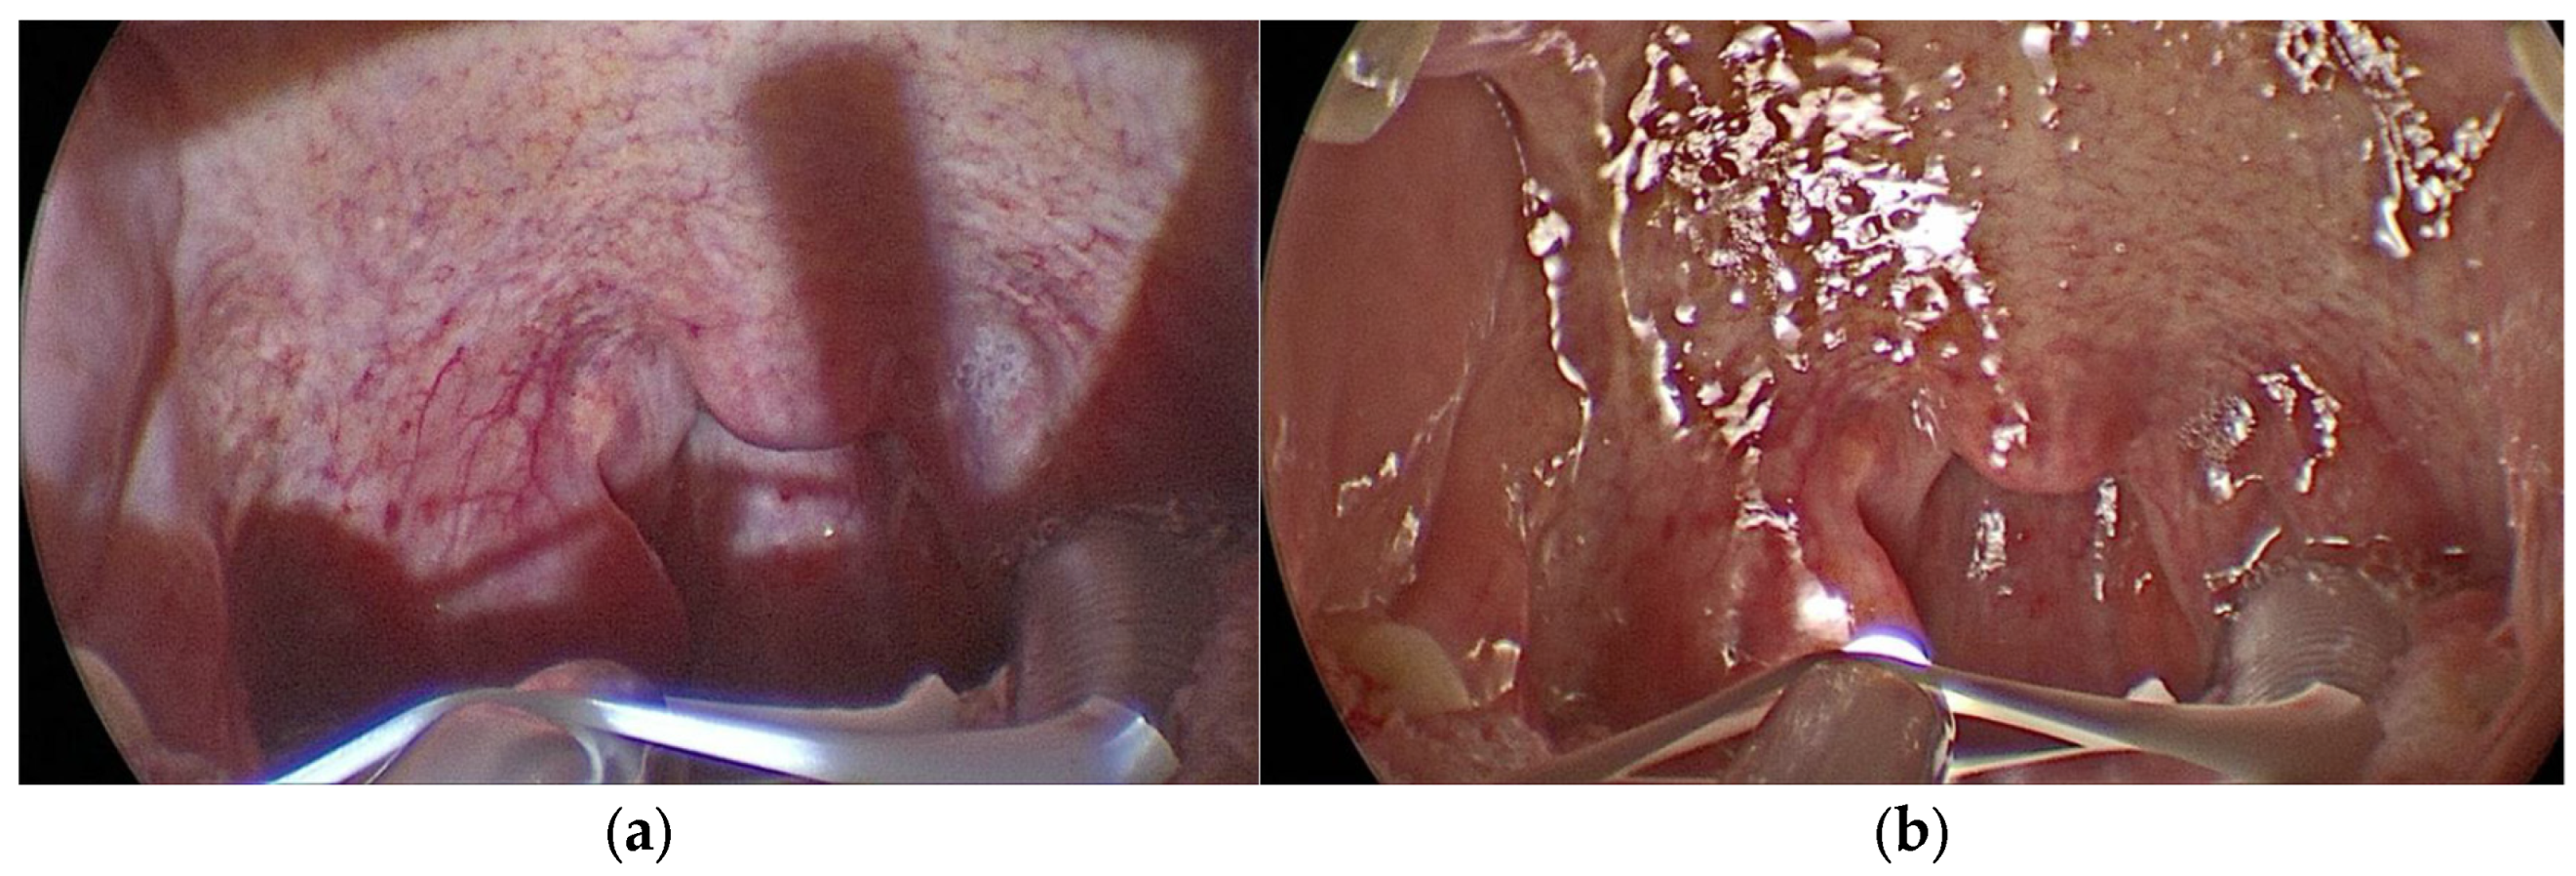

2.2. Surgical Procedure

2.3. The Illumination Device

2.4. Mounting the KLAROTM Device on Tongue Retractor